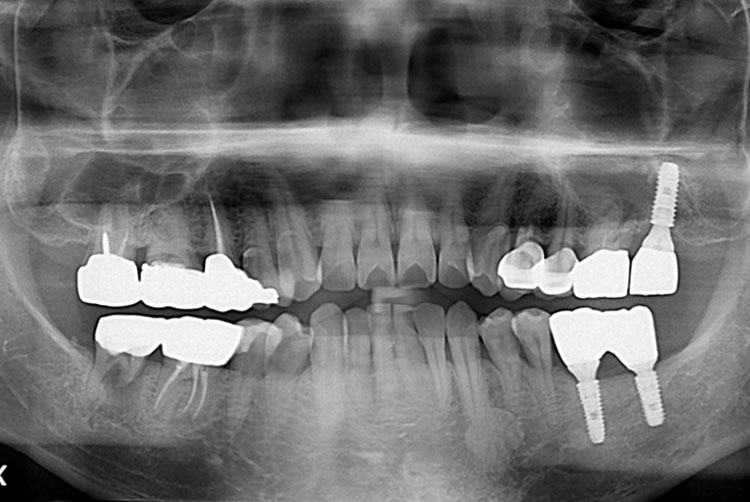

박성우_후.jpg

치료후 : 2006-09-29

세종치과는 많은 환자와 다양한 케이스를 바탕으로 항상 편안한 임플란트 수술을 제공하고자 노력하고,

오래동안 튼튼히 쓸 수 있는 임플란트 수술을 가장 큰 목표로 삼고 있습니다.